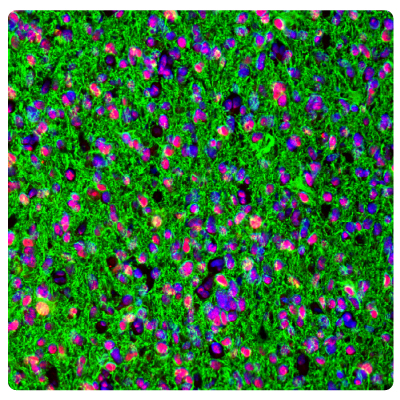

Immunohistochemistry (IHC) plays a vital role in distinguishing between different tumor types. Figures 1 and 2 show some examples of IDH1, ATRX, and GFAP multiplexed IHC-IF staining in different glioma grades.

Figure 2A.ATRX and GFAP in glioblastoma. Multiplexed IHC-IF staining of glioblastoma multiforme showing ATRX (nuclear, in red) and GFAP (cytoplasmic, in green) immunoreactivity in tumor cells using Anti-ATRX antibody and Anti-GFAP antibody. Nuclei were counterstained with DAPI (in blue).

Figure 2B.ATRX and IDH1 in glioblastoma. Multiplexed IHC-IF staining of glioblastoma multiforme showing ATRX (nuclear, in red) and IDH1 (cytoplasmic, in green) immunoreactivity in tumor cells using Anti-ATRX antibody and Anti-IDH1 antibody. Nuclei were counterstained with DAPI (in blue).